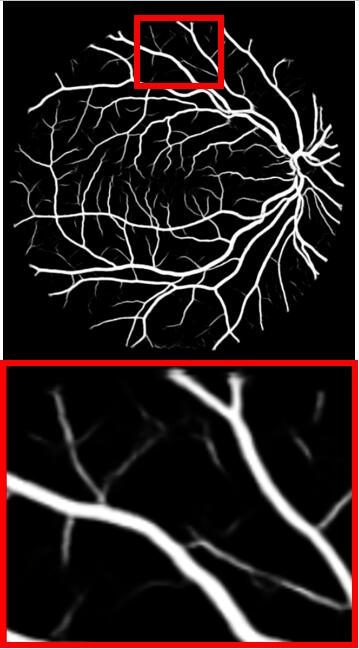

Refer to caption

(a) Input

(b) GT

(c) M-Net

(d) AG-Net

(e) BL

(f) BLST

(g) Ours

Figure 4: Example results for DRIVE. M-Net, AG-Net, and BL disregard some edge structures, which are very similar to textures. Conversely, by decomposing structures and textures, BLST gains better discrimination power and detects more tiny structures. Comparing (f) and (g), when adding the texture block, more tiny boundary structures are detected.

We remove the texture block, structure loss ssubscript𝑠{\mathcal{L}}_{s}, and texture loss tsubscript𝑡{\mathcal{L}}_{t} from STD-Net and name the baseline model as BL. The model BLST is formed by adding the structure-texture loss into BL. Fig. 4 shows a test example, including the ground truth vessel (GT) and segmentation results obtained by M-Net, AG-Net, BL, BLST, and the proposed STD-Net. The experimental results of BL and BLST are shown in Table 3.